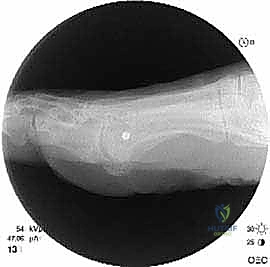

الخطوة الرابعة: الإطالة والطعوم العظمية (Bone Grafting)

يتم إبعاد طرفي العظم المقصوص بلطف للوصول إلى الطول التشريحي المطلوب (والذي تم حسابه مسبقاً في صور الأشعة). لملء الفراغ الناتج عن الإطالة، يتم استخدام طعم عظمي (Bone Graft).

* الطعم الذاتي (Autograft): غالباً ما يتم أخذ قطعة صغيرة من العظم من كعب المريض (عظم العقب) أو من عظم الحوض، وهو الخيار الأفضل لأنه يحفز الالتئام السريع.

* الطعم الصناعي أو العظم البنكي (Allograft): يمكن استخدامه في بعض الحالات لتجنب إحداث جرح إضافي.